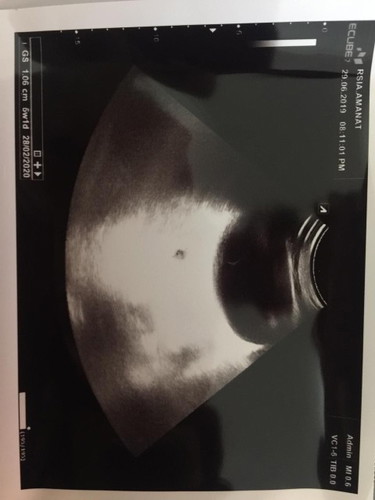

Assalamualaikum bunda, mau tanya ini hasil usg aku, berdasarkan usg usia baru 5 minggu smntara berdasarkan hpht sudah 7 minggu.. lebih akurat mana yaj bund ? Dan pertanyaan paling galau mnurut bunda ini ada isinya kan bunda ??? Soalnya aku sering sakit perut tp nggk ada flek